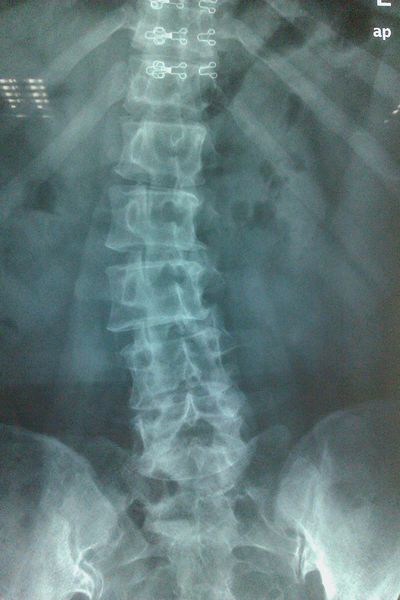

您患过腰痛吗?您都是在什么情况下出现腰痛呢?以我的诊疗经验来说,即使是在大街上随机抽样问这两个问题,我相信大多数人的回答都会是肯定的。因为腰疼这个病症的确极其常见,尤其是40岁以上的中老年人。给大家看个X光片,就知道我们的腰如果不注意保护和锻炼会是什么样子了: